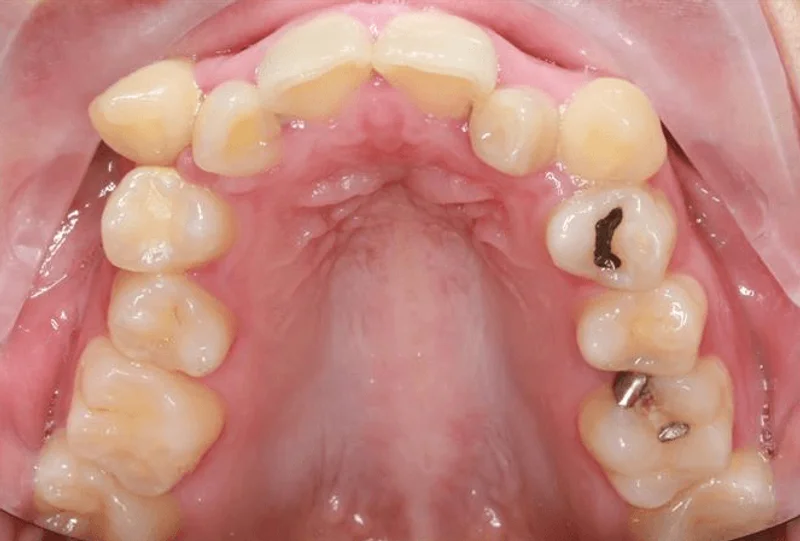

Upper Occlusal

Upper Occlusal - Before Treatment

Before

This Las Vegas Adult Female patient presented with severe crowding upper and lower, and multiple teeth in crossbite. Dr. Benson determined that she would need extractions to correct this patient's malocclusion. She was treated with metal Pitts 21 brackets in 28 months. We are thrilled with her smile transformation!